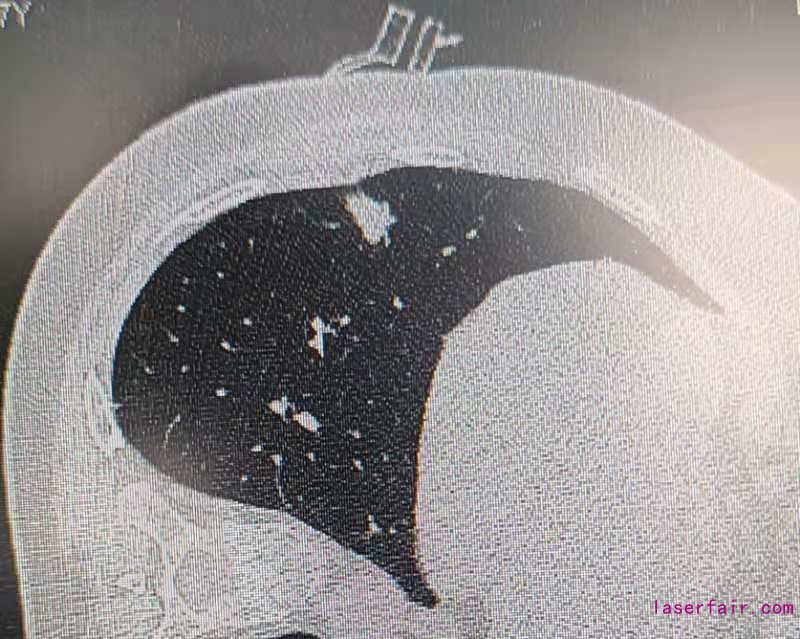

近日,蘭州大學(xué)第一醫(yī)院胸外科應(yīng)用3D打印手術(shù)導(dǎo)航系統(tǒng),結(jié)合術(shù)中CT實(shí)現(xiàn)肺部病變的超精準(zhǔn)定位。此項(xiàng)技術(shù)填補(bǔ)該省相關(guān)領(lǐng)域的空白。

伴隨胸部CT篩查的普及,早期肺部腫瘤發(fā)病率逐年增加,外科治療是唯一根治手段。這類疾病手術(shù)的難點(diǎn)在于病灶偏?。?lt;1cm)、質(zhì)地軟(磨玻璃型結(jié)節(jié)),外科術(shù)中難以精準(zhǔn)確定病變位置及切除范圍。蘭州大學(xué)第一醫(yī)院胸外科利用3D打印技術(shù),個(gè)體化定制肺小結(jié)節(jié)的術(shù)前定位導(dǎo)板,結(jié)合目前國(guó)際先進(jìn)水平雜交手術(shù)平臺(tái),術(shù)中CT設(shè)備輔助外科醫(yī)師術(shù)中定位肺結(jié)節(jié)位置。對(duì)比傳統(tǒng)定位技術(shù),3D導(dǎo)板定位導(dǎo)航系統(tǒng)可極大簡(jiǎn)化肺結(jié)節(jié)定位操作步驟,降低輻射暴露劑量,提高手術(shù)精度,減少肺部手術(shù)損傷。為患者加速康復(fù)打下了堅(jiān)實(shí)的基礎(chǔ)。